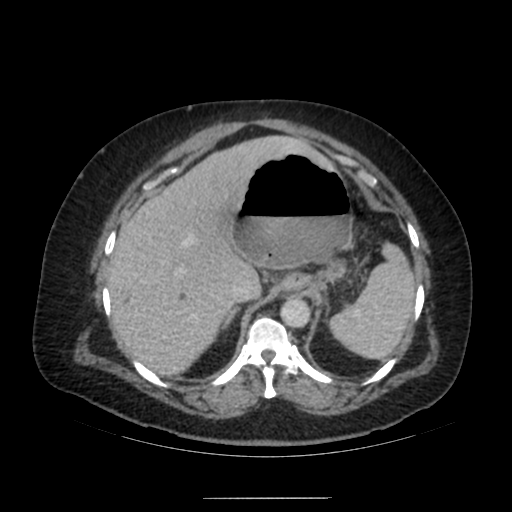

수술 후 복강 내 상태를 확인하기 위해 복부 CT를 촬영함.

복부 CT를 보면 수술부위 쪽으로 아주 큰 pocket이 형성되고 그 안쪽에 air-fluid level이 형성되어 있는 것을 확인할 수 있음.

해당 부분은 수술로 문합을 한 GE junction 쪽으로 염증의 위치로 생각할 수 있음.

추후 외과 과장님께 들어보니 sleeve op. 이후 leakage가 주로 생기는 위치는 gastro-esophageal junction 쪽이며, 천장으로는 liver(간), 좌측으론 spleen과 omentum이 있어 주변으로 염증이 퍼지지 않고 위 사진처럼 갇힌 형태의 염증이 생성된다고 한다.

1. About 14cm sized air-containing complicated fluid collection around the stomach.

: probable leakage at sleeve gastrectomy site.